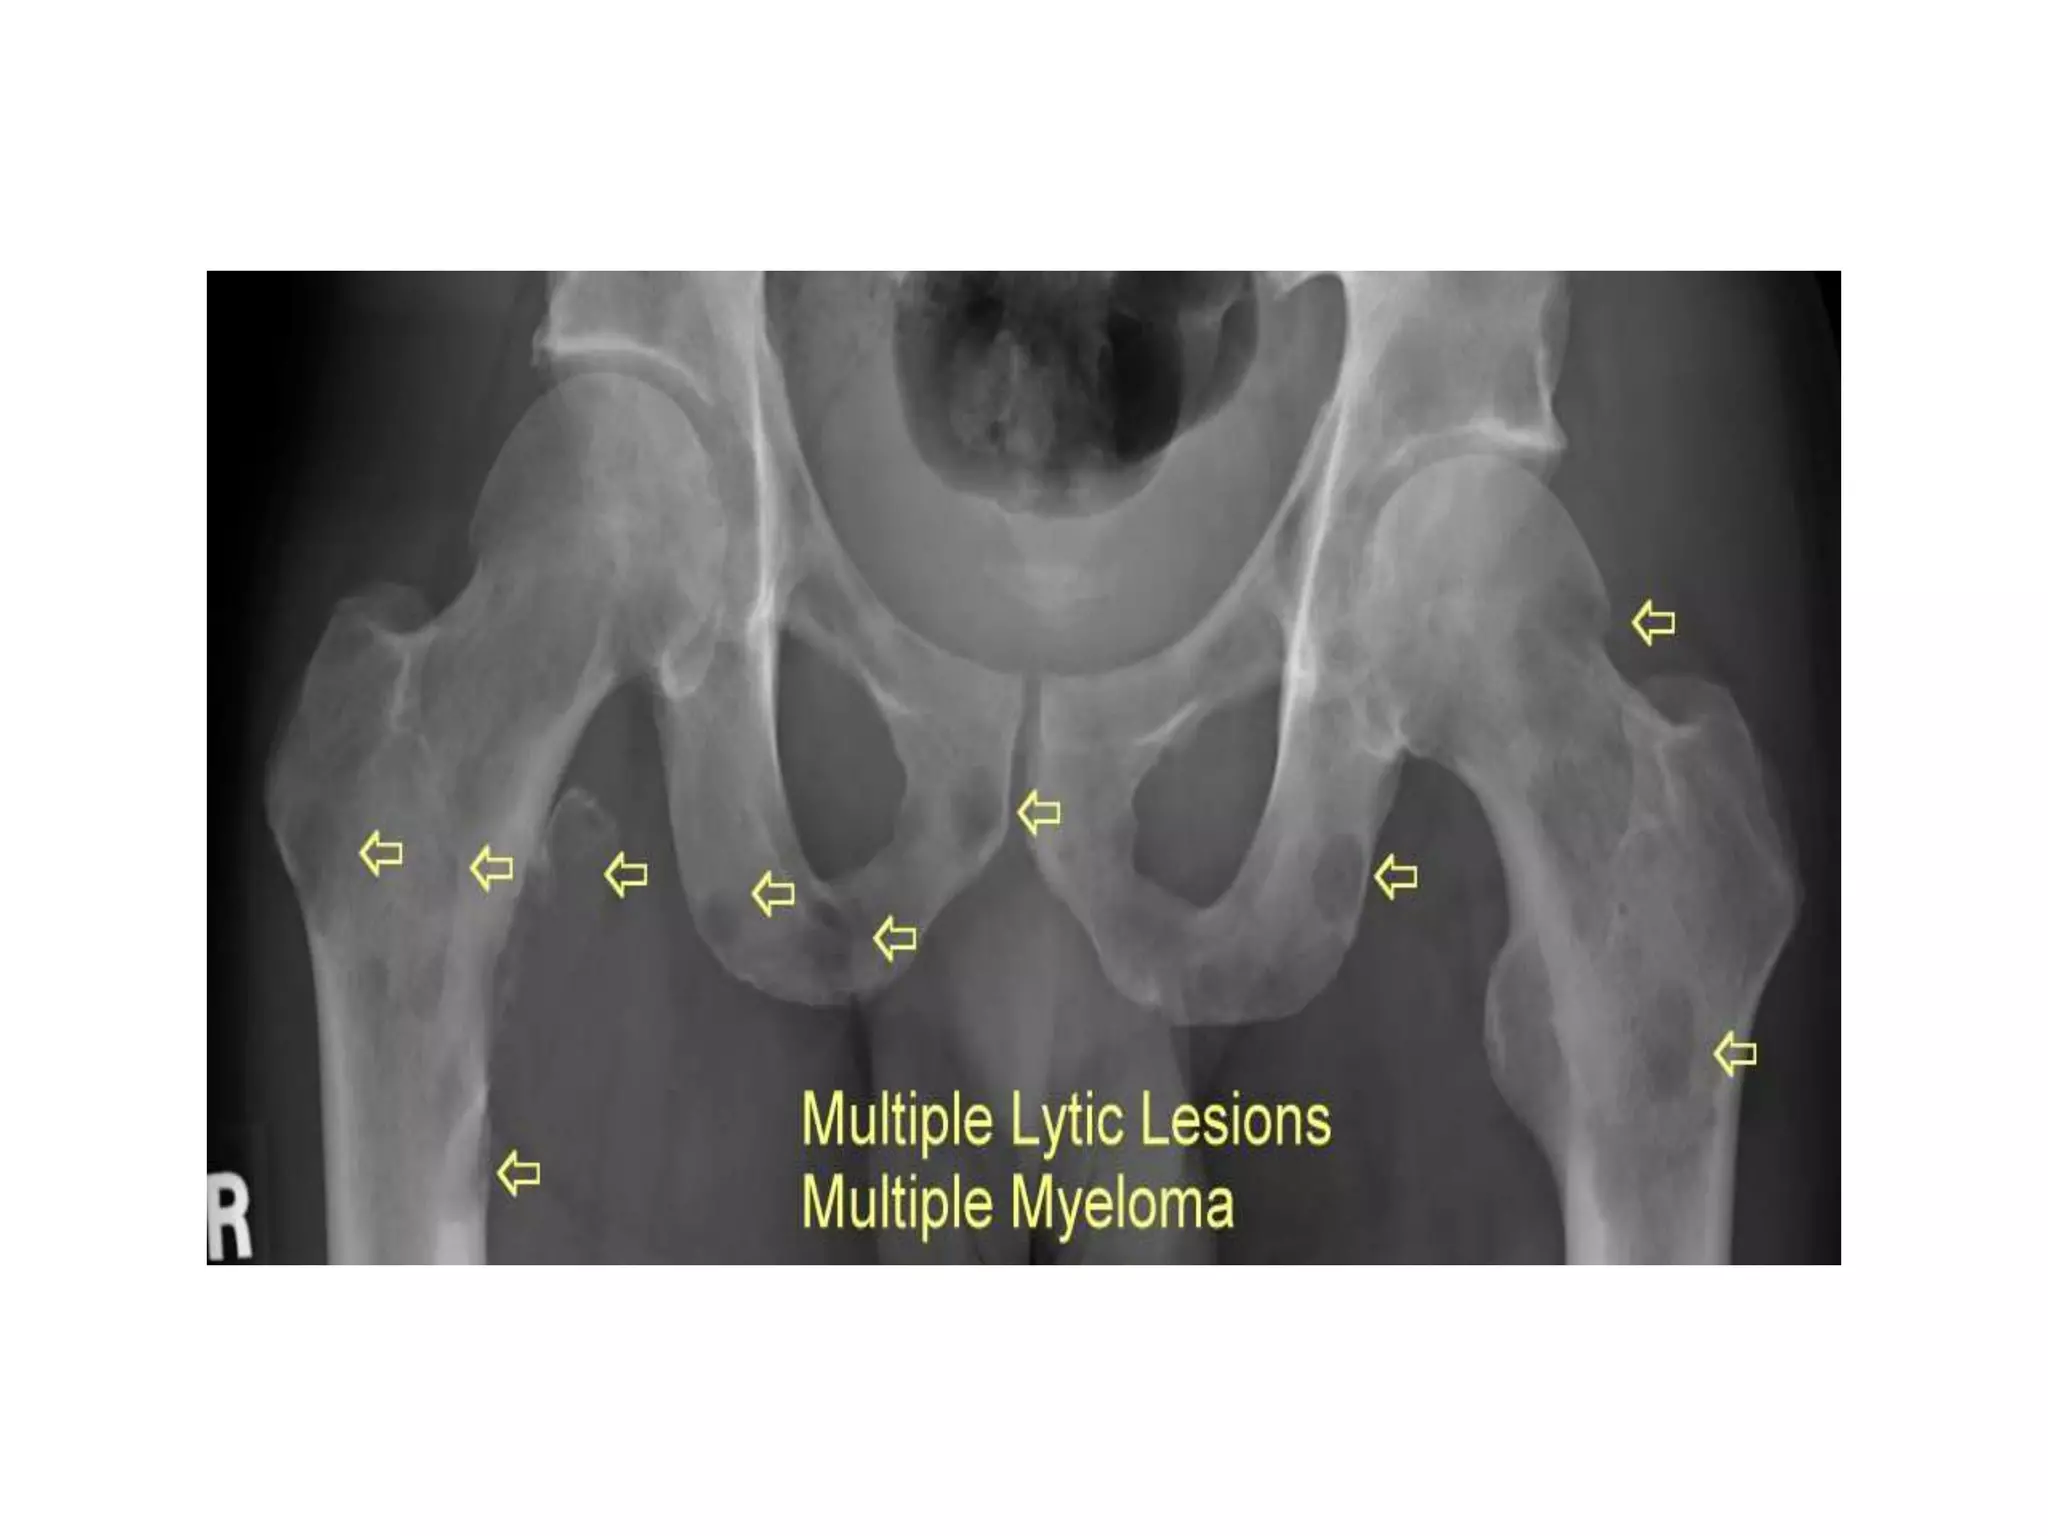

iii. Radiological examination

•Multiple punched out lesion in the skull and flat

bone

•Pathological wedge collapse of the vertebrae

(more than one) in the thoracic spine. Pedicles

are usually spared.

•Diffuse, severe rarefaction of bones

1. Differential diagnosis

i. Multiple myeloma

• Patient’s age is 60 (common age is 45-65)

• Male (common in male)

• Complains of backache (vertebrae is one of the common site)

• Increasing pain (common presenting complaint especially in the

lumbar and thoracic spine)

• Serum electrophoresis shows monoclonal gammopathy (usually

found in association with multiple myeloma)

• High ESR level